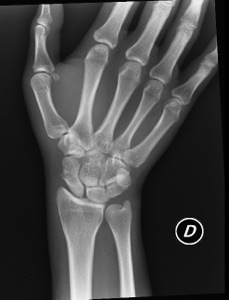

Il portiere, durante l’incontro con la New Team, ha riportato un piccolo ma fastidioso infortunio al pollice della mano e ora potrebbe non recuperare per la prossima gara di Challenge.